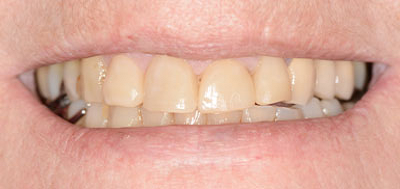

Le patient a 52 ans et il s’est usé les dents avec une brosse-à-dent très dure. Il a pensé bien faire en buvant beaucoup de jus de citron et en se faisant des bains-de-bouche à la chlorhéxidine. Nous sommes face à une abrasion d’origine mécanique et chimique et à des colorations dentaires d’origine médicamenteuse.

Des images photographiques en 2D et des images en 3D ont été couplées pour concevoir la réhabilitation du sourire et la proposer au patient.

Résultat final.